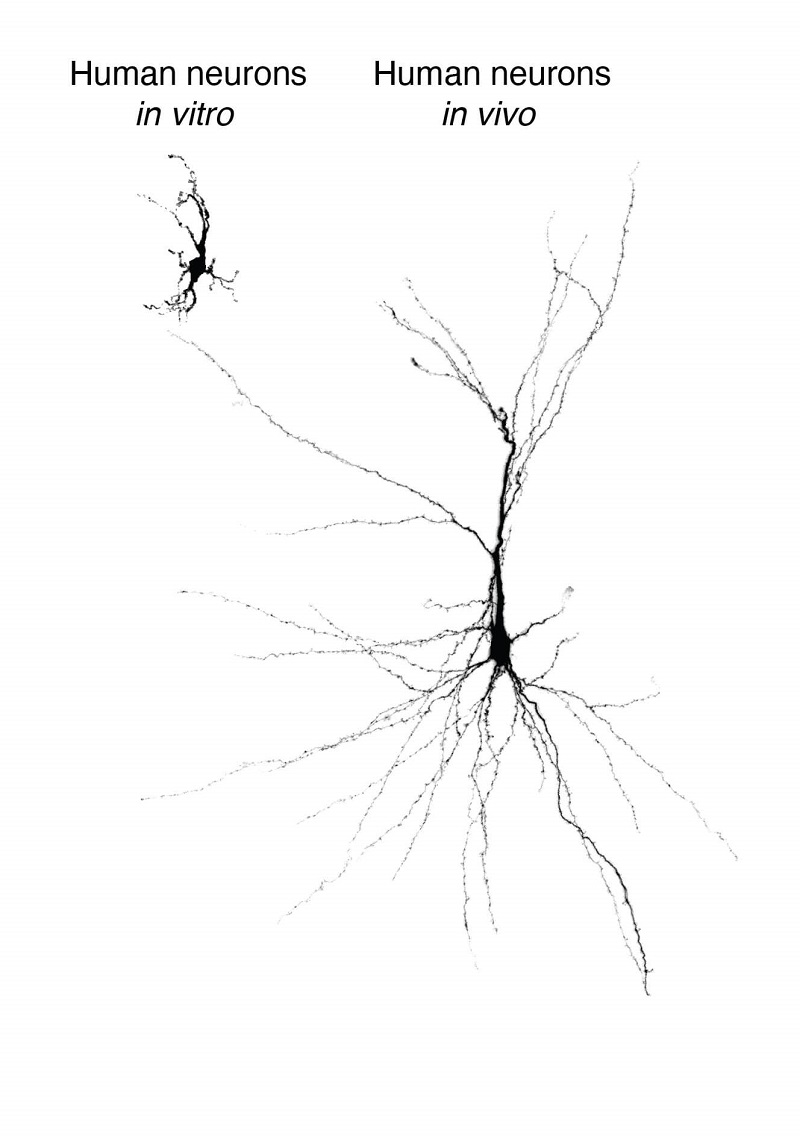

来自干细胞的重建人类神经元,在培养皿中维系并移植到大鼠大脑皮层中。

图片来源:斯坦福大学